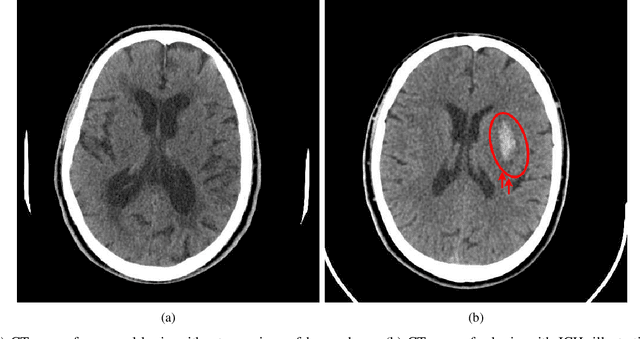

Abstract:Intracranial hemorrhage (ICH) is a critical medical emergency caused by the rupture of cerebral blood vessels, leading to internal bleeding within the skull. Accurate and timely classification of hemorrhage subtypes is essential for effective clinical decision-making. To address this challenge, we propose an advanced pyramid vision transformer (PVT)-based model, leveraging its hierarchical attention mechanisms to capture both local and global spatial dependencies in brain CT scans. Instead of processing all extracted features indiscriminately, A SHAP-based feature selection method is employed to identify the most discriminative components, which are then used as a latent feature space to train a boosting neural network, reducing computational complexity. We introduce an entropy-aware aggregation strategy along with a fuzzy integral operator to fuse information across multiple CT slices, ensuring a more comprehensive and reliable scan-level diagnosis by accounting for inter-slice dependencies. Experimental results show that our PVT-based framework significantly outperforms state-of-the-art deep learning architectures in terms of classification accuracy, precision, and robustness. By combining SHAP-driven feature selection, transformer-based modeling, and an entropy-aware fuzzy integral operator for decision fusion, our method offers a scalable and computationally efficient AI-driven solution for automated ICH subtype classification.

Abstract:Intracranial hemorrhage (ICH) refers to the leakage or accumulation of blood within the skull, which occurs due to the rupture of blood vessels in or around the brain. If this condition is not diagnosed in a timely manner and appropriately treated, it can lead to serious complications such as decreased consciousness, permanent neurological disabilities, or even death.The primary aim of this study is to detect the occurrence or non-occurrence of ICH, followed by determining the type of subdural hemorrhage (SDH). These tasks are framed as two separate binary classification problems. By adding two layers to the co-scale convolutional attention (CCA) classifier architecture, we introduce a novel approach for ICH detection. In the first layer, after extracting features from different slices of computed tomography (CT) scan images, we combine these features and select the 50 components that capture the highest variance in the data, considering them as informative features. We then assess the discriminative power of these features using the bootstrap forest algorithm, discarding those that lack sufficient discriminative ability between different classes. This algorithm explicitly determines the contribution of each feature to the final prediction, assisting us in developing an explainable AI model. The features feed into a boosting neural network as a latent feature space. In the second layer, we introduce a novel uncertainty-based fuzzy integral operator to fuse information from different CT scan slices. This operator, by accounting for the dependencies between consecutive slices, significantly improves detection accuracy.